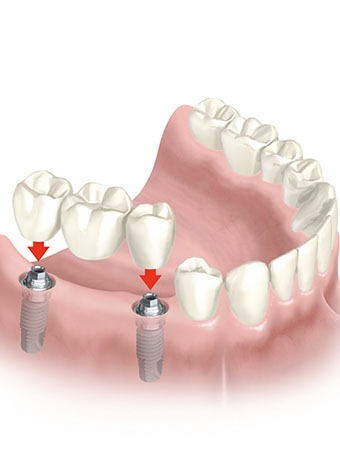

L’assemblaggio tra Impianto e Protesi

Tolta definitivamente la Vite di Guarigione si avvitano i Pilastri, ciascuno per ogni Impianto.

Ogni Pilastro farà da sostegno alla Protesi.